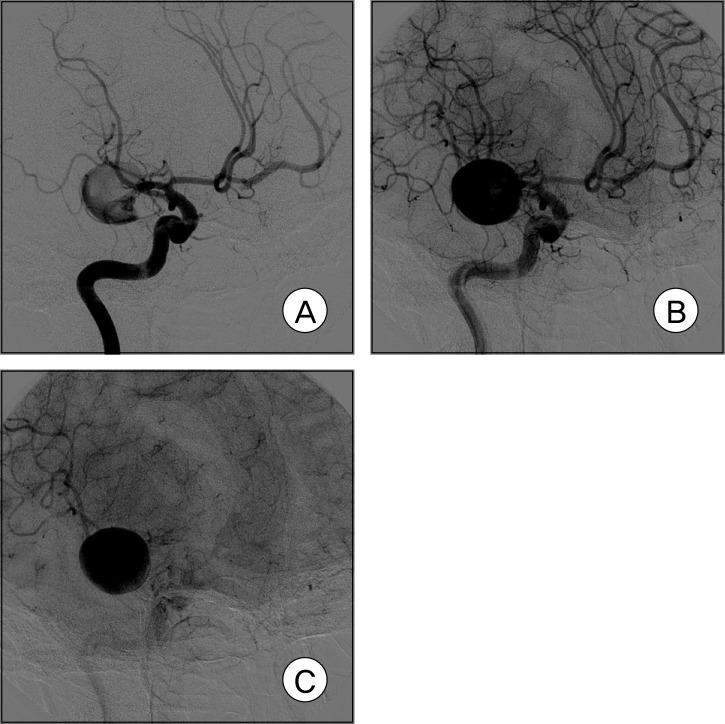

There are few observation papers regarding the natural history of an aneurysm. We report on a case of a completely occluded middle cerebral artery (MCA) aneurysm. A 47-year-old female patient presented with a headache and was diagnosed with rupture of a right MCA aneurysm. Due to a high risk of direct neck clipping, she received conservative treatment after craniotomy and wrapping of her aneurysm. The patient's condition showed improvement, with complete occlusion of the aneurysm and considerable reduction of the aneurysm in size after approximately three years. This is a rare case of an aneurysm of MCA that showed spontaneous resolution. Finally, on the angiogram, characteristics of an aneurysm to occlude spontaneously will be presumed based on literature reviews.

关于动脉瘤自然史的观察性论文很少。我们报告一例大脑中动脉(MCA)动脉瘤完全闭塞的病例。一名47岁女性患者因头痛就诊,被诊断为右侧MCA动脉瘤破裂。由于直接夹闭颈部的风险较高,她在开颅手术和包裹动脉瘤后接受了保守治疗。大约三年后,患者病情有所改善,动脉瘤完全闭塞且大小显著缩小。这是一例罕见的MCA动脉瘤自发消退病例。最后,基于文献综述,在血管造影上推测动脉瘤自发闭塞的特征。